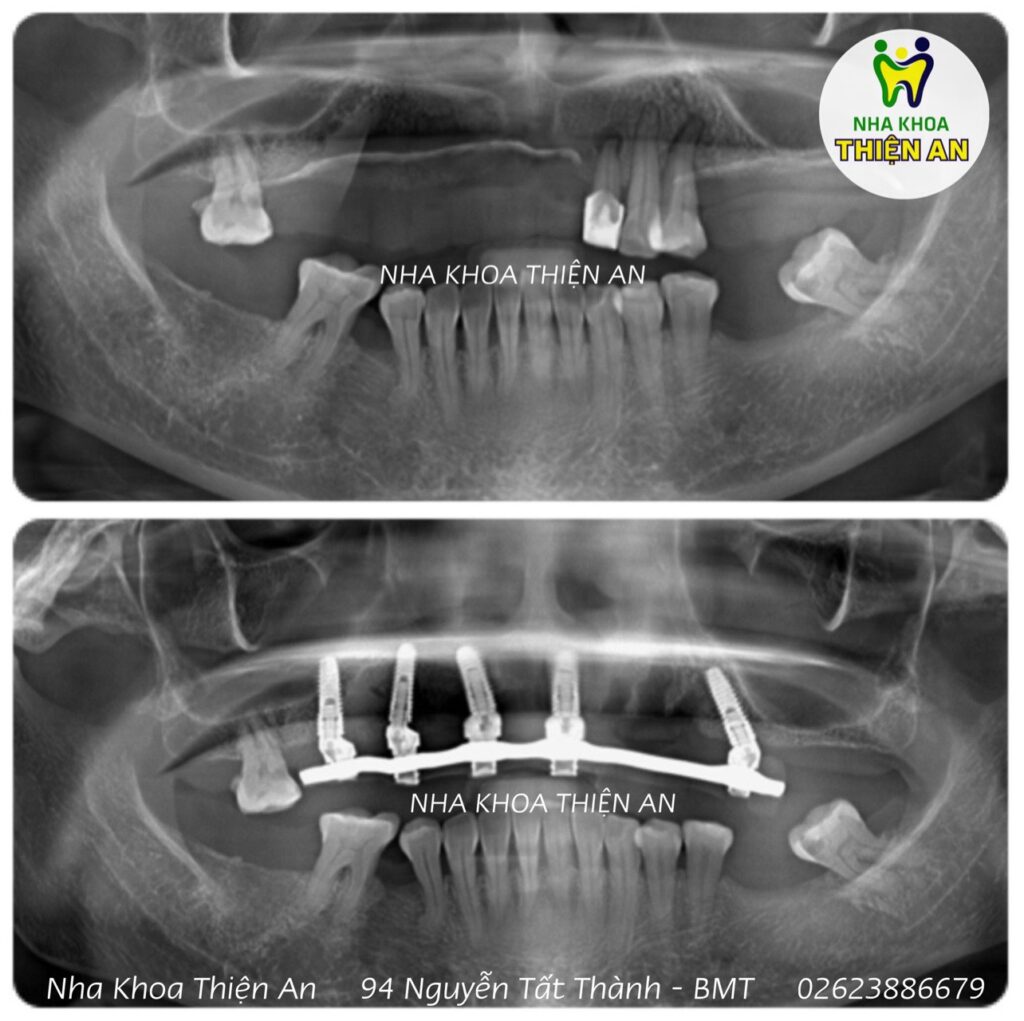

Cấy implant toàn hàm tại tại nha khoa Thiện An BMT – Đăk Lăk có răng tạm tức thì cho cô chú ăn nhai luôn.

Full jaw implant at Thien An BMT dental clinic – Dak Lak, temporary teeth are immediately available for you to eat and chew